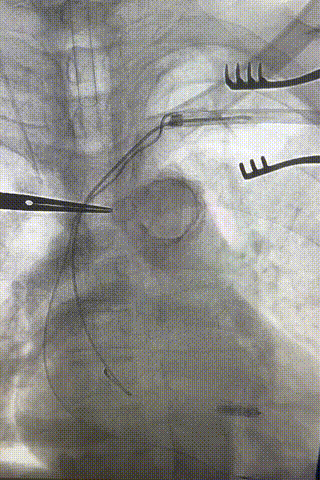

心室电极拔除:因锁定钢丝牵引力不足,以外鞘前向分离为主,激光鞘辅助消蚀,逐步分离粘连组织(图23-36),耗时近1小时,激光鞘联合外鞘经三尖瓣进入心室,发现电极与心室壁严重粘连。因牵引力不足,术者凭借心脏解剖经验精准调整角度,利用激光鞘逐步分离粘连组织,最终经外鞘成功剥离电极,可见长段粘连组织(图27-30)。

图23-26